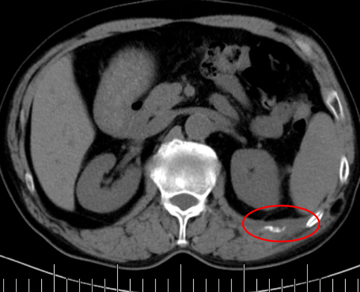

老年男性,68歲,肺癌術(shù)后肋骨轉(zhuǎn)移,痛疼難忍。

當(dāng)日痛疼緩解